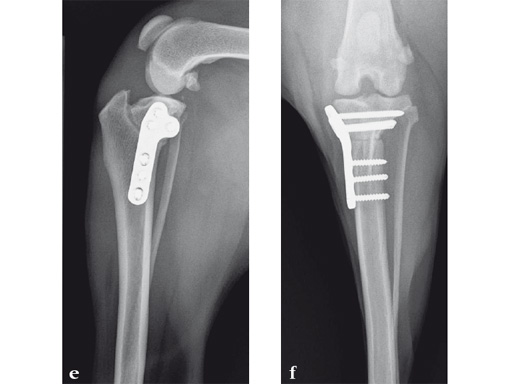

Tibial plateau leveling osteotomy can be performed through a small medial incision over the proximal tibia when using arthroscopy to inspect and treat intraarticular structures. Patients will typically walk on the leg soon after surgery. It is recommended to restrict activity for 8 weeks to walking only. The osteotomy typically is healed within 8 weeks and return to function can begin progressively after radiographic evidence of healing. Long-term prognosis is excellent. The implants are typically left in place for the life of the patient, unless implant removal is necessary due to clinical problems.

An 11-year-old female, spayed, 13.6 kg cocker spaniel had a complete tear of the left cranial cruciate ligament. A 2.4 mm TPLO plate was perfect for this dog due to the excessive slope of the tibial plateau (30) and the size of the dog. Three 2.4 mm locking screws were used proximally and three 2.4 mm cortical screws were used distally. The contour of this plate matches the contour of the bone almost perfectly. The plate is also designed to optimize the angle of the proximal screws so that they engage the most dense and thickest bone and avoids penetration of the stifle joint.

A 10-year-old female, spayed, 6.0 kg cat had a partial tear of the left cranial cruciate ligament, meniscal mineralization, and a medial meniscal tear. The cat was treated with a partial meniscectomy and TPLO . A 2.0 mm TPLO plate was perfect for this cat due to the slope of the tibial plateau (25) and the size of the cat. Three 2.0 mm locking screws were used proximally and three 2.0 mm cortex screws were used distally. The contour of this plate does not perfectly match the contour of the proximal tibia, but use of locking screws in this segment avoids any potential angulation of the segments as the screws are tightened. The cat healed uneventfully and returned to normal function.